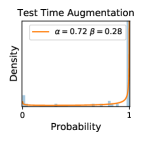

To model how different classifiers will respond to a given input , we assume that the prediction from classifier is sampled from a beta distribution that is characterized by two parameters by and . We further assume that is fixed to the same constant value for all ’s. Under this assumption, each input can be described by ( can be calculated since is fixed), easing further analysis. The Severity Level (SL) of the case represented by image can be characterized by the parameter . The larger the value of , the more severe the case of is. When and are close, the case is ambiguous as the distribution shifts towards being symmetric (i.e. signifying much disagreement among classifiers) rather than being one-sided (i.e. consensus among classifiers that is negative or positive). We provide a set of examples in Figure 2 and also Figure S.8 in the supplementary materials showing how the beta distribution can be used to capture diverse predictions given by an ensemble learner.

We conducted a case study on diagnosing diabetic retinopathy with ensembles of DL models. For benchmarking the performance of our ensemble-based solutions under the scheme described in Sec.3.3, we used two popular collections of diabetic retinopathy image data, the Kaggle Diabetic Retinopathy dataset [22] (hereafter referred to as “Kaggle-DR”) and the Messidor-2 dataset [23], each respectively consisting of and high resolution images. Diabetic retinopathy is graded into five SLs, as displayed in Figure 2. Following the problem setup used in previous papers [24], we trained models to distinguish the referable (SL2-4) cases from the non-referable ones (SL0 & SL1) (see Section B.1 for more detailed descriptions). We also tested our trained ensemble models on two o.o.d. image datasets (ImageNet [25] and CIFAR-10 [26]) to examine their capabilities of identifying o.o.d. inputs (see Section B in the supplementary materials).

In contrast, the MC-dropout method showed the worst overall performance among the three, as it can be seen from the high ratios of SL0 examples among the uncertain negatives in Figure 4. The histograms in Figure 2 provides another perspective to look into the phenomenon, where a decent proportion of MC-dropout model’s predictions on SL0 inputs entailed low confidence (far from 0 or 1), which from another angle explained why MC-dropout was less specific in terms of lower FNP; many no-DR inputs (i.e. SL0) were erroneously assigned high uncertainty by MC-dropout models.

It is still an open question why the evaluated MC-dropout networks signaled relatively high uncertainty on SL0 & SL3 & SL4 data that are less likely to be ambiguous. We conjecture that much of the “uncertainty” indicated by disagreement among test-time dropout samples actually reflects the stochastic nature of dropout networks rather than the real decision uncertainty associated with the data. It is worth noting that the MC-dropout model we evaluated was not weak per se; they all achieved above Area Under Curve (AUC) scores on test sets. The weakness of individual test-time samples (which explains their low-confidence predictions on SL0 & SL3 & SL4) might have been hidden when they are aggregated into an ensemble—a well-known advantage of ensemble learning. Our results suggested that the uncertainty information given by implicit ensemble methods such as MC-dropout and TTA might not be as reliable as that from explicit ensemble approaches (e.g., stacking ensembles). Similar findings on MC-dropout can be found in some previous papers [1].